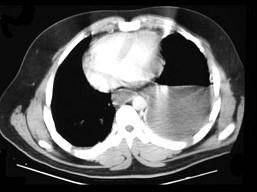

问题 35岁,男,因车祸入院,呼吸困难、发绀、上腹痛,请结合胸片和CT选择最可能的诊断 ( )

选项 A、膈麻痹 B、液气胸 C、胸腔积液 D、膈膨升 E、膈疝

答案 E